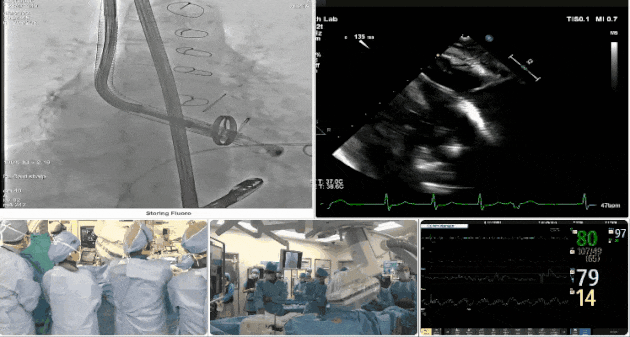

術(shù)中TEE觀察夾持件的位置

術(shù)后DSA

術(shù)后超聲評估瓣膜穩(wěn)定性良好,無瓣周漏

手術(shù)過程

術(shù)者采用經(jīng)右側(cè)頸靜脈入路的方式將輸送器送入患者心臟內(nèi),在TEE及DSA引導下調(diào)整輸送器頭端角度,使得輸送器與三尖瓣瓣環(huán)平面垂直。在輸送器進入右心室后釋放室間隔錨定裝置,而后釋放瓣葉夾持件(2個耳片結(jié)構(gòu))成垂直狀態(tài)。在TEE及DSA確定夾持件固定至三尖瓣葉根部且位于右室側(cè)后釋放人工瓣心房側(cè)盤片。隨后調(diào)整瓣膜同軸性以及室間隔錨定件位置(貼合室間隔),前推藏針管并固定,進而釋放室間隔錨定裝置,并再次確認瓣膜位置、穩(wěn)定性及同軸性,合攏輸送鞘后撤出輸送器,最終順利完成LuX-Valve Plus人工三尖瓣瓣膜的植入。